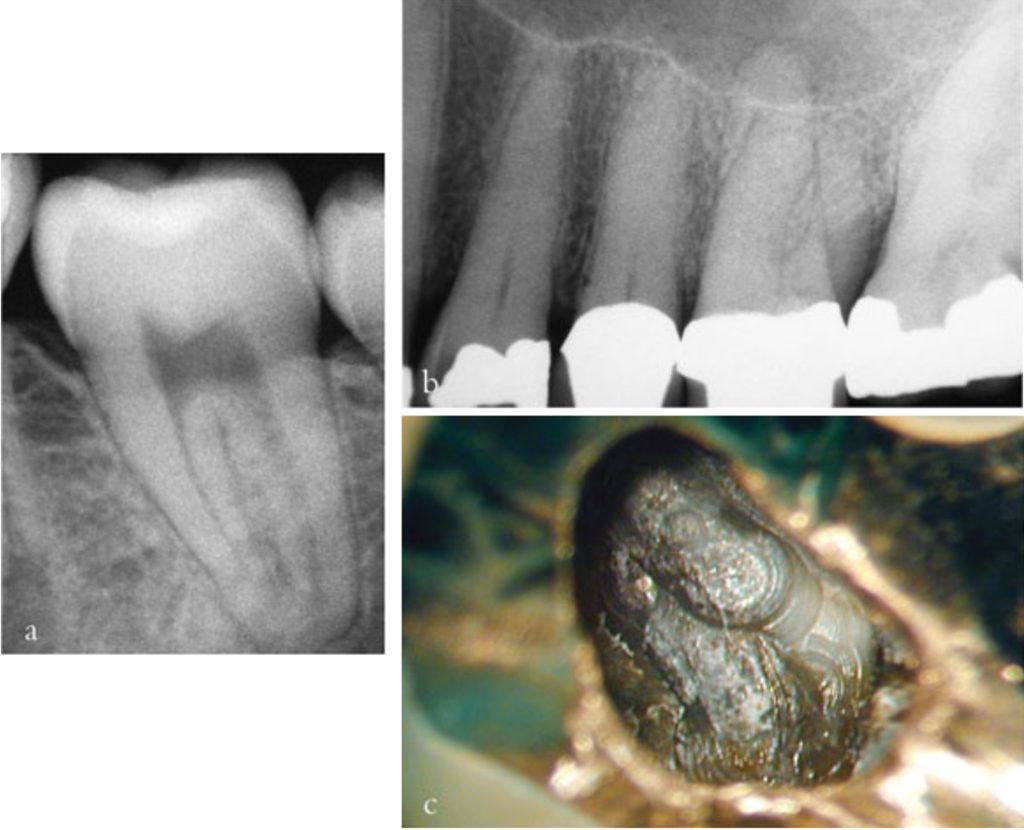

Trám bít ống tủy

Mục tiêu của trám bít là ngăn ngừa tái nhiễm khuẩn ống tủy đã được khử khuẩn; chôn vùi các vi sinh vật còn sót lại trong ống tủy và ngăn chặn dịch từ mô quanh chóp xâm nhập vào ống tủy, vì nó có thể là nguồn dinh dưỡng cho các vi sinh vật còn tồn tại.

Kỹ thuật lèn ngang là một phương pháp trám bít đơn giản, chi phí thấp và đáng tin cậy, được giảng dạy rộng rãi tại các trường nha khoa trên toàn thế giới. Mặc dù kỹ thuật này có thể trám kín được ống tủy chính, nhưng nó không thích hợp với những hệ thống ống tủy phức tạp có các nhánh nhỏ, khe hoặc bất thường, cũng như những ống tủy có dạng thuôn không liên tục, chẳng hạn như nội tiêu.

Để khắc phục vấn đề về độ khít sát và độ chảy của vật liệu, các kỹ thuật sử dụng gutta-percha “nhiệt dẻo” hiện nay đã được ứng dụng rộng rãi, cho phép tạo ra khối trám bít đặc hơn và hoàn chỉnh hơn, ngay cả trong những trường hợp có giải phẫu phức tạp.

Kỹ thuật nhồi dọc sử dụng một cây nhồi đã xác định trước, làm nóng bằng điện để nhồi dọc gutta-percha vào phần ba chóp ống tủy. Độ thuôn phía chóp của ống tủy đã sửa soạn và sự khít sát của côn gutta-percha tạo nên dạng kháng thích hợp, giúp ngăn vật liệu bị đẩy ra ngoài lỗ chóp. Phần giữa và phần thân ống tủy sau đó được “trám bít ngược” bằng gutta-percha nhiệt dẻo, bơm bằng thiết bị dạng súng như Obtura II®.

Tất cả các cây lèn ngang và cây nhồi dọc đều phải vừa thụ động trong lòng ống tủy; thận trọng tránh dùng lực quá mức khi lèn vật liệu trám bít để không gây nứt hoặc gãy chân răng.

Vật liệu trám bít ống tủy cần kết thúc ở chóp răng tại điểm giới hạn của quá trình tạo hình (điểm thắt chóp). Ở phía thân răng, vật liệu trám bít nên dừng lại cách miệng ống tủy từ 1–2 mm. Trong những trường hợp có tiêu xương nha chu thì phần trám bít nên dừng lại cách mào xương ổ 1–2 mm, nhằm tránh việc vật liệu trám bị lộ ra môi trường miệng qua các ống ngà còn thông.